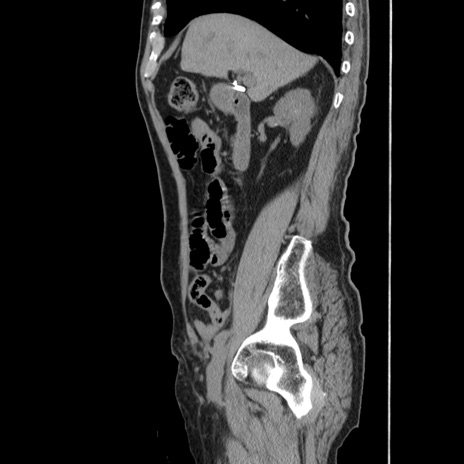

症例24(矢状断像)

【症例】80歳代男性

【主訴】左側腹部痛、嘔吐

【現病歴】本日早朝より左腹部に痛みあり。昼頃嘔吐認めたため、救急要請。

【既往歴】直腸癌(Mile手術)、胆摘

【身体所見】意識清明、BT 35.9℃、BP 221/93mmHg、SpO2 97%(RA) 、腹部:左ストーマ周囲に限局性の腹部膨隆あり。 膨隆部自発痛・圧痛あり・軟。

【データ】WBC 7700、CRP 0.09